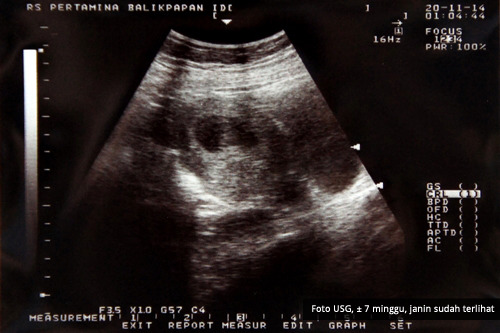

Nanda Novita Hertanti :.: June 2013

Nanda Novita Hertanti :.: June 2013

Hasil USG Umur Janin 9 Minggu | Our family home’s Blog

Hasil USG Umur Janin 9 Minggu | Our family home’s Blog

Hasil USG | Febriyan Indriana

Hasil USG | Febriyan Indriana